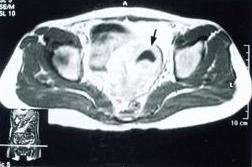

外陰腫瘤外陰腫瘤發生的部位以大陰唇最多,約占71.2%,其次為小陰唇、陰蒂、尿道口周圍,再次為前庭大腺及會陰。病變大體表現視其部位及病變早晚而不同。病變早期,常為局部小硬結,高出皮膚或黏膜,以後自行破潰,或因搔癢抓破而成潰瘍。或者起病時突出表皮者即成乳頭狀或小菜花狀,組織脆而易出血或脫落。或開始即為小潰瘍,其潰瘍基底部邊緣較硬,潰瘍常有出血或感染。

病變進一步發展至晚期,表現或為大潰瘍,向深部或鄰近器官浸潤,外陰局部可大部分被“蠶食”而缺損;或呈“火山口”樣;或局部結節性包塊;或者表現為大菜花狀,基底部浸潤可深或稍淺。表面質脆極易脫落而感染潰爛。前庭大腺腫瘤少見,開始即為橢圓形硬塊,位於大陰唇的後1/3處,其表麵皮膚可較長時間不與腫塊愈著。發生於汗腺者更罕見,表現為圓形、扁平或高起的結節,位於大陰唇外側或內側。前庭尿道癌開始為多個小結節,形成乳頭狀贅生物,包繞尿道口或位於其一側,進一步發展則潰破,沿尿道海綿體及陰道口侵犯。